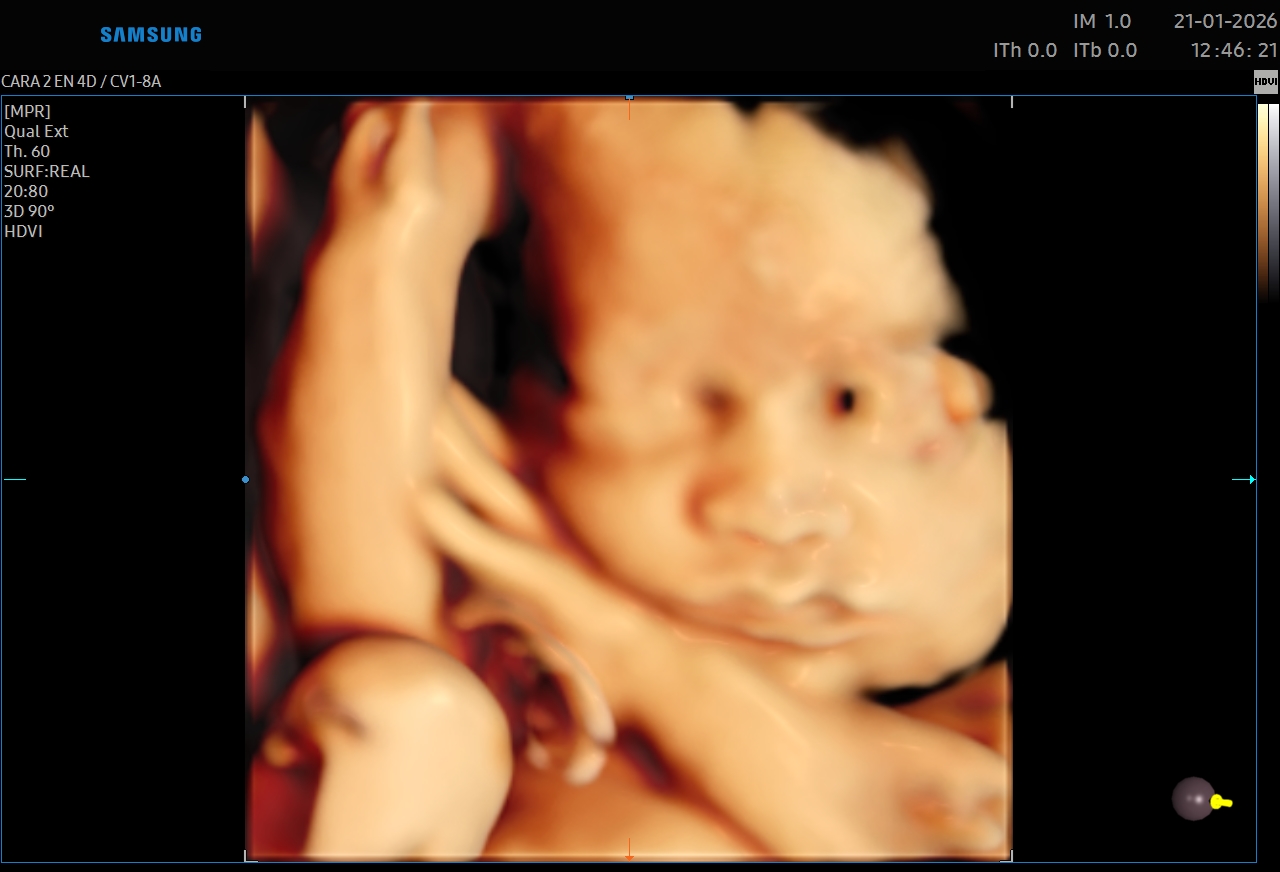

Ecografías 5D

La ecografía 5D es una experiencia única que te permite ver a tu bebé con un nivel de realismo sorprendente, capturando detalles como sus gestos, expresiones y movimientos en tiempo real.

Gracias a esta tecnología avanzada, podrás observar el rostro de tu bebé con mayor claridad, creando un vínculo emocional aún más especial antes de su nacimiento. Es el momento perfecto para compartir con tu familia y guardar recuerdos inolvidables de esta etapa tan importante.

Además de ser una experiencia hermosa, este estudio se realiza con equipos de alta tecnología y bajo supervisión médica, garantizando seguridad tanto para la mamá como para el bebé.